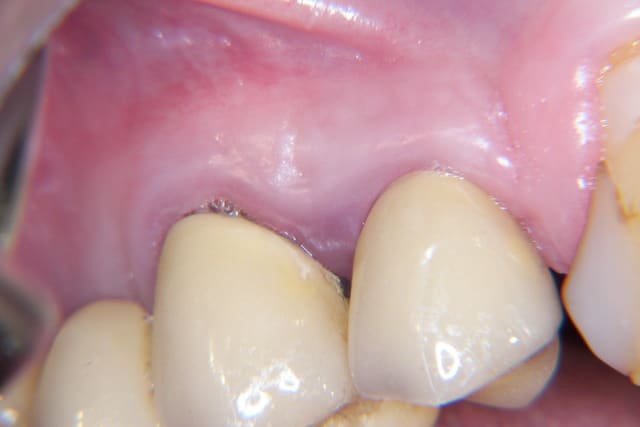

Tu as tout à fait raison PXAV, je fais ce type d'expansion pour rétablir le bombé sur les cas ou s'est visible.

sinon quand je fais expansion et implant standard, oui, je refait le galbe vestibulaire

Voici un cas ou ça a été fait

Associes tu un conjonctif enfoui pour la réalisation du galbe vestibulaire ou bien est elle obtenue seulement avec une expansion laterale osseuse ?

Dans ce cas précis, il n'y a eu qu'une expansion latérale, pas de conjonctif.

Cela dit il n'y pas de contre indication à faire un conjonctif enfoui.

pour illustrer ces propos, voilà un cas clinique récemment réalisé.

Amicalement